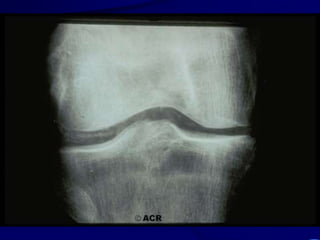

OSTEOARTRITIS

CORRELACION ANATOMO-RADIOLOGICA

PATOLOGIA RADIOLOGIA

Fibrilación y erosión cartilaginosa Pinzamiento articular

Prolifer. celular en hueso subcondral Esclerosis ósea

Intrusión de LS o contusión ósea Quistes subcondrales

Proliferación marginal Osteófitos

Distorsión capsular y ligamentaria Deformidad y desalineación

Osteoartritis: Características Generales

•Osteófitos

•Pinzamiento

articular

•Quistes

subcondrales y

esclerosis

•Desalineación